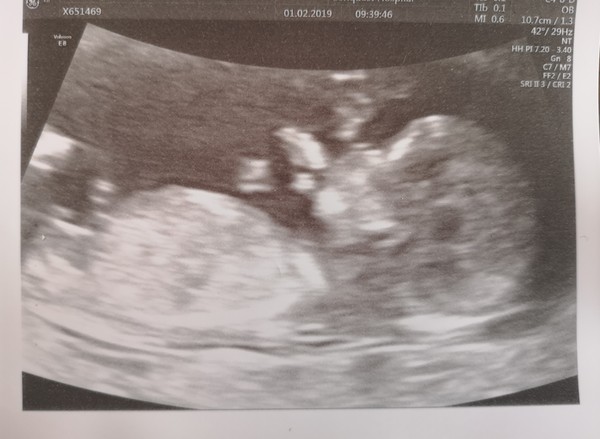

Hubby and I went for our 12 week scan yesterday (at 12+4) and baby was measuring at 13+1! Thinking it might be tall like hubby! 😂 So due date moved from 12th Aug to 8th! I

@CalmerComber you missed me probly coz the thread moves so fast. and also scan pic was rubbish so got passed by very quickly lol.